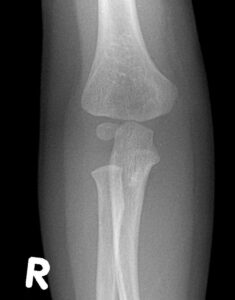

[toggle title=”Medial Epikondiler Kırıklar” state=”close”]

Çoğunlukla 10-14 yaş arası çocuklarda görülür.

Yaralanma direkt travma sonucu olabileceği gibi fleksör kas grubunun oluşturduğu avülsiyon sonucu ya da dirsek çıkığına sekonder de olabilir.

Medial epikondil kırıklarının yarısına yakınında eşlik eden dirsek çıkığı da görülür. Bu hastalarda dirsek redükte edildiğinde medial epikondil kırığı da redükte olur.

Kırık parçanın eklem içinde kalması nedeniyle redüksiyon yapılamayan durumlarda ya da kırığa eşlik eden ulnar sinir yaralanması varlığında cerrahi tedavi gerekir.